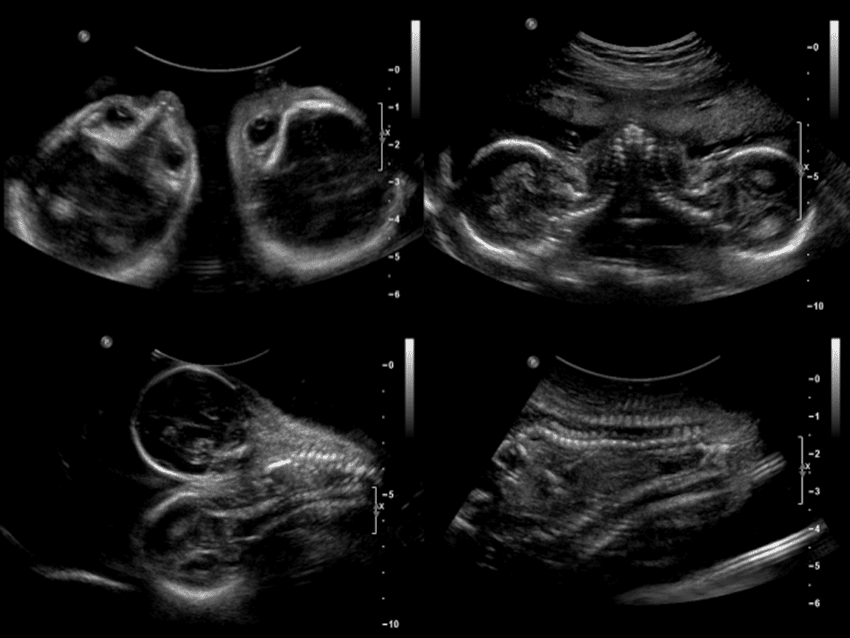

Imaging Tests and Their Effectiveness

Imaging tests are vital for spotting fibroids and understanding them. Ultrasound is the main tool used. It shows if fibroids are present, how big they are, and where they are. Sometimes, MRI (Magnetic Resonance Imaging) is used for a closer look, if ultrasound results are unclear or if there’s concern about other issues.

These tests help not just in finding fibroids but also in checking for other causes of bleeding. This includes endometrial polyps or cancer.